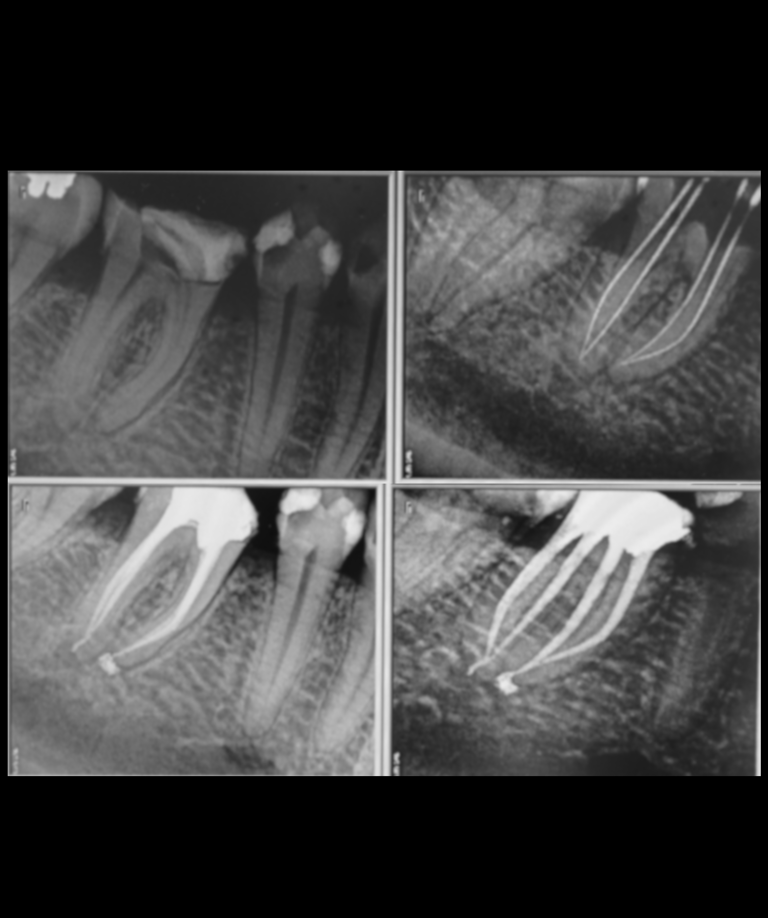

Parodontologie pour l'omnipraticien

Diagnostic et traitement